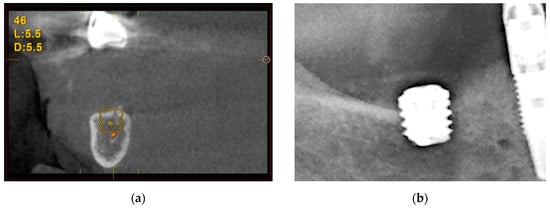

3.3.1. Vertical Bone Atrophy in the Mandible

The first case is shown in Figure 7 and corresponds to vertical bone atrophy in the lower jaw with a residual bone height of 4 mm above the alveolar nerve (Figure 7a). The placement of the implant was performed just above the nerve leaving a portion of the implant neck exposed buccolingually (Figure 7b). The exposed area of the implant was covered using the patient’s own bone mixed with PRGF-Endoret® (Figure 7c). The slow-drilling procedure for the implant-site preparation (125 rpm without irrigation) allows the recovery of bone from the patient that, once mixed with PRGF-Endoret®, forms a flexible membrane with embedded bone particles. This membrane can be shaped to fill biological gaps or to overcorrect situations like the one described above [17]. Figure 7d,e shows how already, 4 months after the placement of the implant, the regenerated bone is covering the implant completely. The stability of this bone is maintained 5 years after the surgery (Figure 7e).

Figure 7.

Vertical bone atrophy in the jaw with a residual bone height of 4 mm (a). Insertion of the dental implant leaving a part of the implant exposed, which was covered using bone recovered from the site preparation mixed with PRGF-Endoret® (b,c). At 4 months (d,e), vertical bone regeneration can be observed covering the implant (yellow arrow). Stability of the regenerated bone at 5 years follow-up (f).